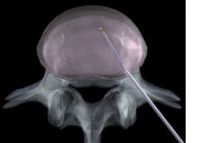

- osteoporosebedingte Wirbelkörperfrakturen